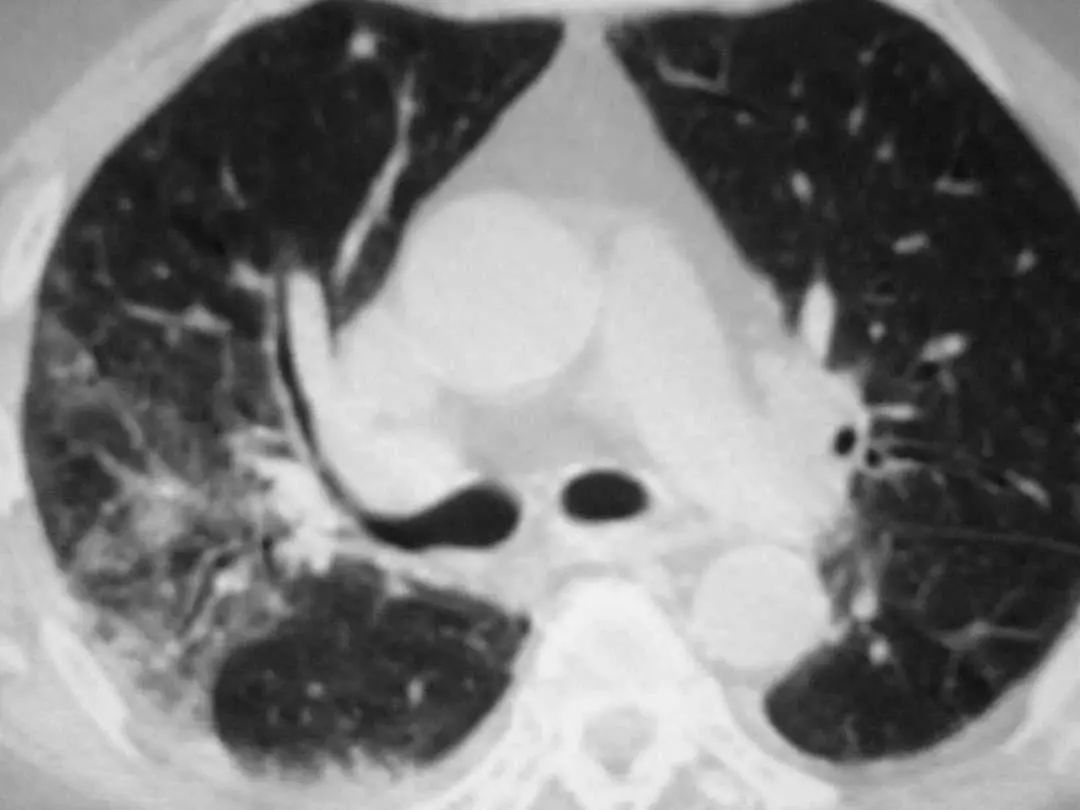

图1.2 细菌性肺炎。双肺下叶肺炎患者影像。

图1.3 细菌性肺炎。早期右肺中叶肺炎的影像学表现。